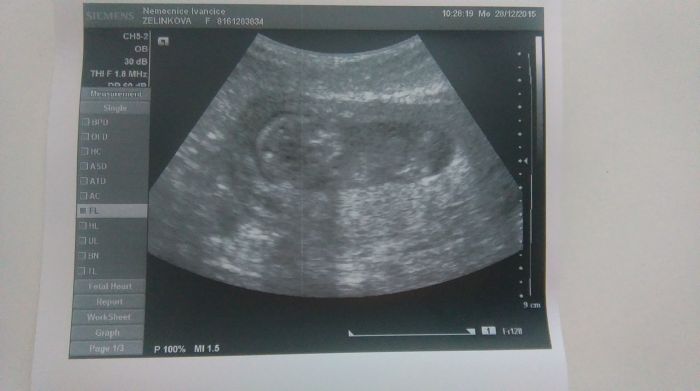

a všechno v pohodě.....dál z vyšetření mám krev v moči nevím čemu to přisuzovat prý jestli jsem nešpinila říkám že ne že to bych věděla tak jestli ta ledvina už zlobí nebo z toho břicha včera netuším....vyšetřil mě říkal že všechno je v pořádku pak mě dělal ultrazvuk tak odpovídá týdnu termín zustava akorát to prý nebude žádný obr teprve ted máme tech 7 cm a odpovídáme takže zase mrnousek.....krev pokud by byla i přístě tak už mě požene po doktorech.....jinak do poradny za měsíc a napíše mě žádanku na ten velký ultrzvuk at ho nemusím platit....na to břicho mě napsal ten magnosol prej to pomáhá že se natahují vazy a prostě to bolí miminka si dělaj místo pro sebe takže doufám že mám na měsíc od doktorů pokoj a tot vše

fotky z ultrazvuku má teda hrozně vybledlé nechápu.

Tak to je dobré Vlasti.mne dr na tom prediku řekl ze miminko má 10cm ale ten tvůj prďolka to jeste dožene uvidíš ze jo,Jinak ty fotky má opravdu blby.ale hlavne ze je vše v pořádku já jdu do poradny 6.1 zrovna my bude brat stěry z čípku prevence po roce,no a potom utz už se těším